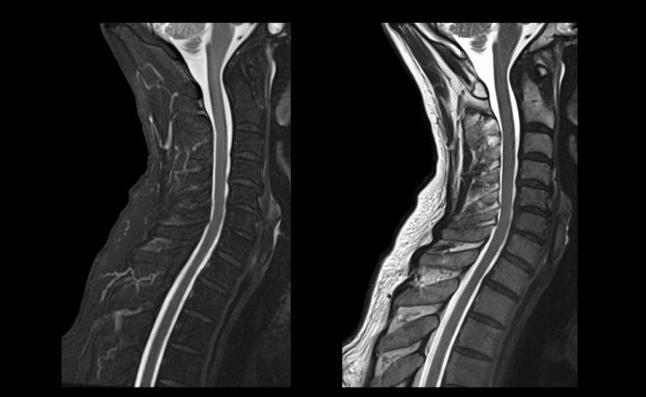

Магнитно-резонансная томография шейного отдела позвоночника | 2 500р. |

Магнитно-резонансная томография грудного отдела позвоночника | 2 500р. |

Магнитно-резонансная томография поясничного отдела позвоночника | 2 500р. |

Магнитно-резонансная томография пояснично-крестцового отдела позвоночника и копчика | 3 000р. |